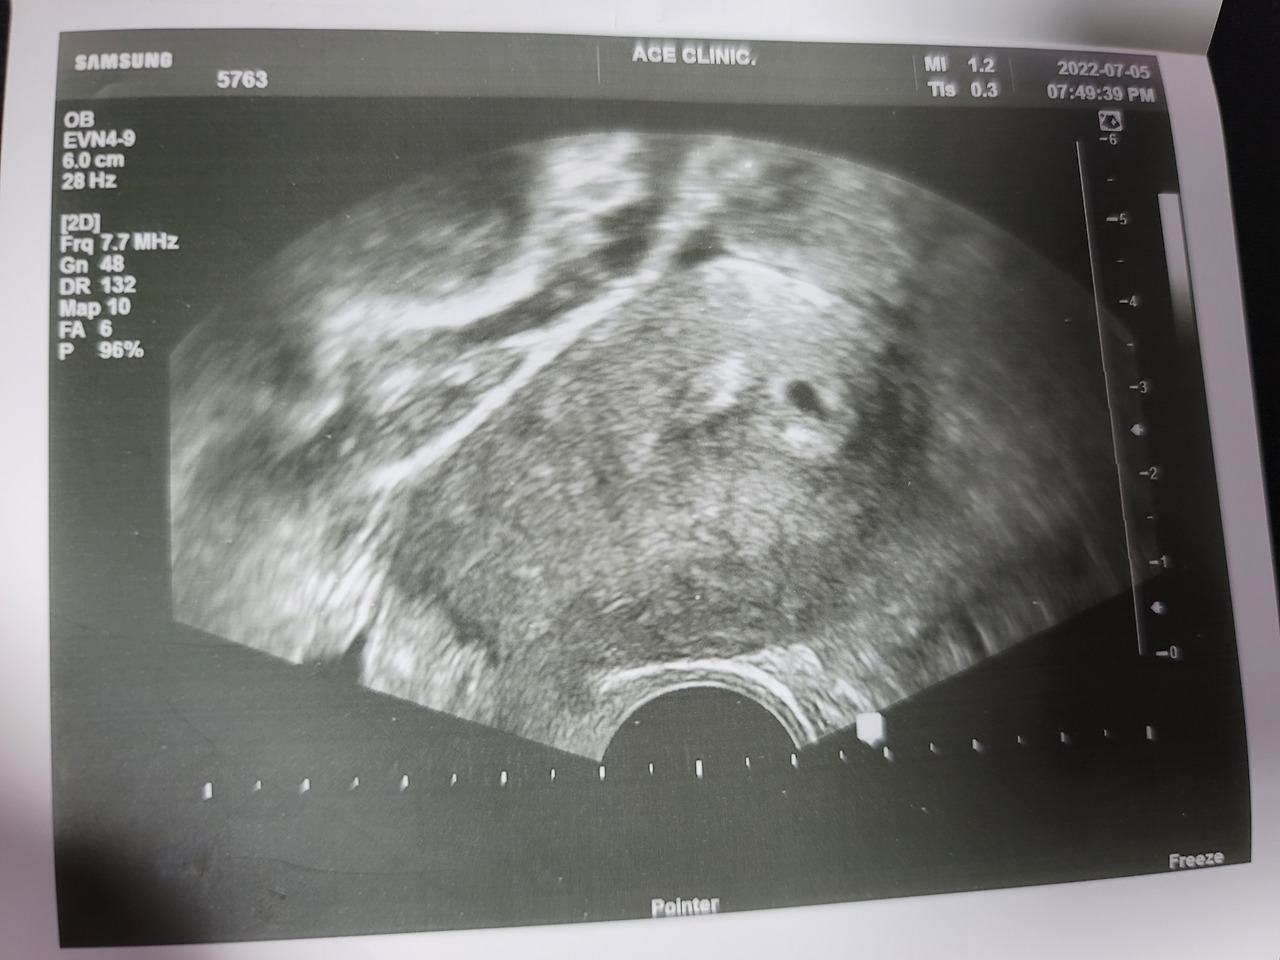

#1. 3일전, 우리 부부에게 아이가 생겼다. 아직은 너무 작은 생명이다. 3주도 채 되지 않았다고 한다. 하지만 앞으로 잘 지켜나가야 한다는 책임감이나 두려움보다, 새로운 세상을 마주하는 설레임이 더 크다. 조금 철없는 예비 부모 일지도 모르겠다.